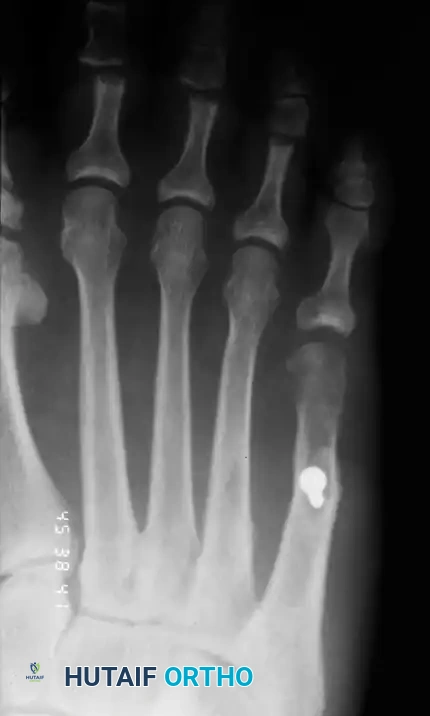

In contemporary orthopedic practice, a bunionette is frequently observed as part of a broader forefoot pathology, most notably the splay foot deformity combined with hallux valgus. The etiology is multifactorial. The head of the fifth metatarsal may be congenitally or traumatically enlarged (Type I deformity). Alternatively, the diaphysis may be angulated laterally (Type II deformity), or there may be a widened fourth-fifth intermetatarsal angle (Type III deformity), making the fifth metatarsal head excessively prominent.

Fig. 80-30 A and B, Bunionette with metatarsus quintus valgus and fifth toe varus.

Fig. 80-31 Bunionette–hallux valgus–splay foot complex. Note lateral angulation of shaft of fifth metatarsal at distal third (arrows).

Associated Surgical & Radiographic Imaging